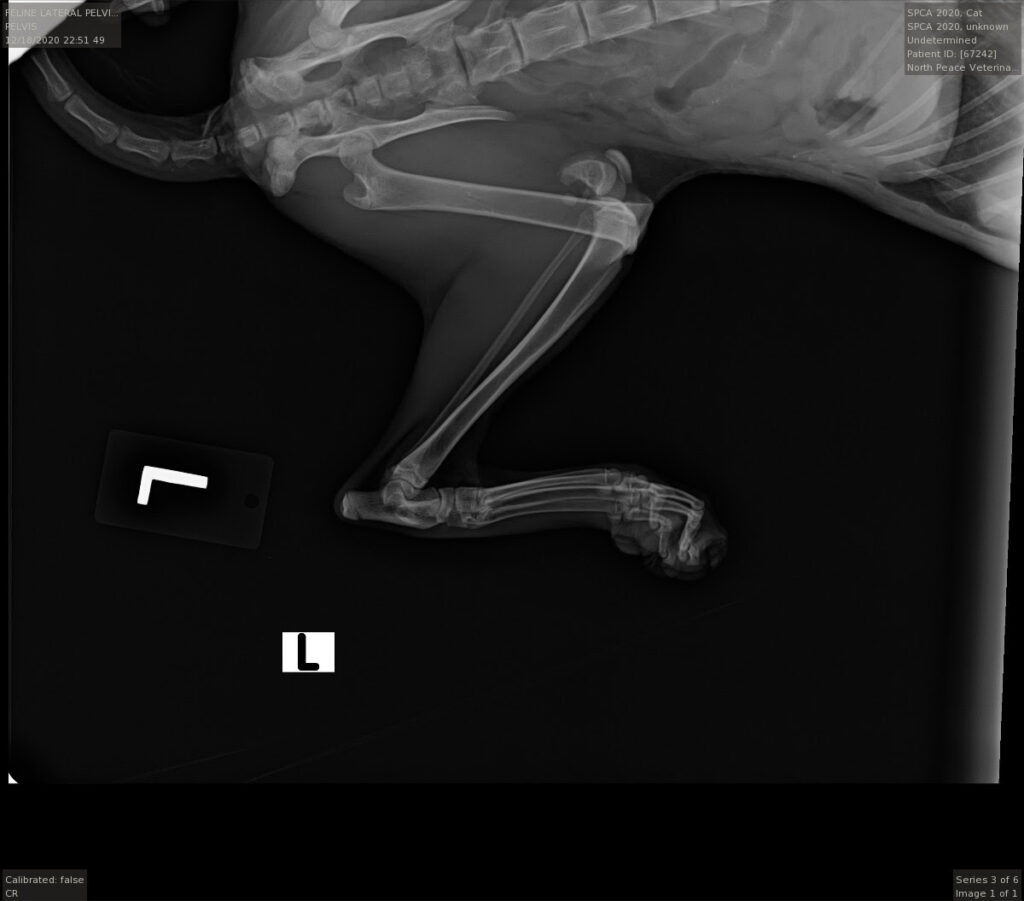

In case it is difficult to see, her long bone is severely fractured directly below the knee joint .